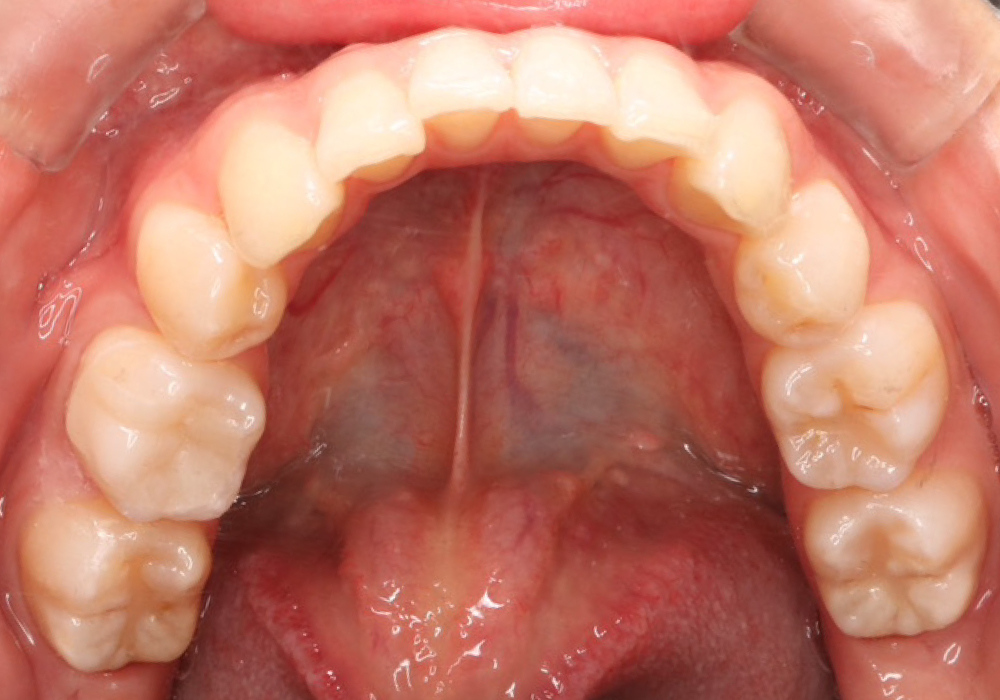

治療後